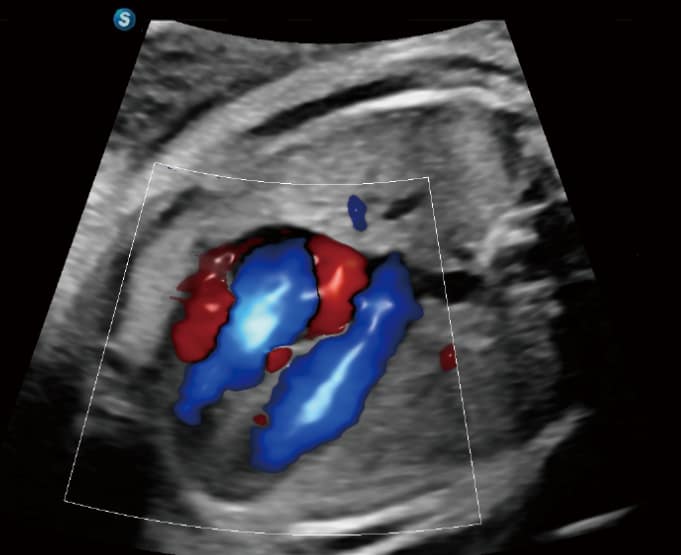

• Bright Flow: Erzeugt eine 3D-ähnliche Darstellung des Farbdopplers ohne Volumenwandler, was die Abgrenzung von Gefäßwänden verbessert.